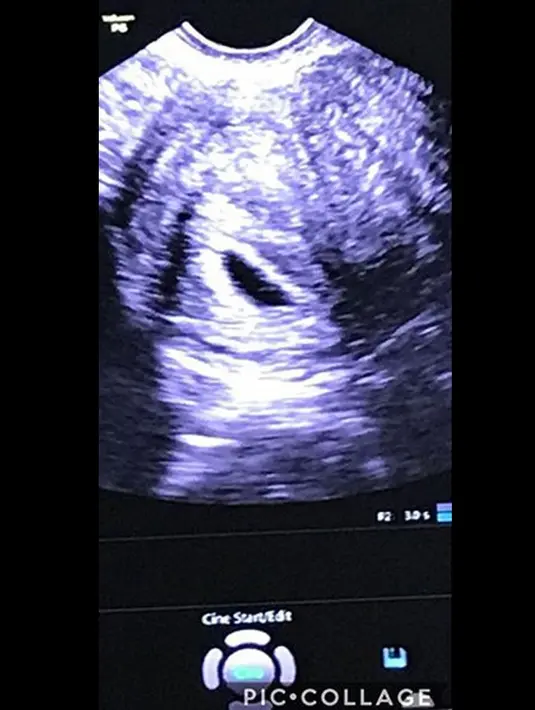

Sempat mengunggah foto hasil USG sebuah janin dan foto anak pertamanya, Azka, pada bulan Desember 2017 lalu menunjukan bahwa saat itu usia kehamilannya sudah lima minggu. (Instagram/kalinaocktaranny)

Kalina Oktarani tengah dirundung duka dan kesedihan yang mendalam setelah mengalami keguguran di usia kandungannya hampir dua bulan. Lewat akun Instagram, Kalina ungkap kesedihan atas kehilangan calon anaknya. (Instagram/kalinaocktaranny)

Dituliskan di unggahan fotonya bahwa Kalina begitu sedih dengan kepergian anaknya ini. Namun ia berusaha untuk ikhlas karena ia sadar bahwa sang pencipta lebih menyayangi malaikat kecilnya itu. (Instagram/kalinaocktaranny)

Meski belum diketahui, namun Kalina yakin anaknya berjenis kelamin perempuan. Ia pun sudah menyiapkan nama, “FALIHA ABIGAIL KAITLYN” (Anak kecil mungil kesayangan, kebanggaan papa yang beruntung). (Instagram/kalinaocktaranny)